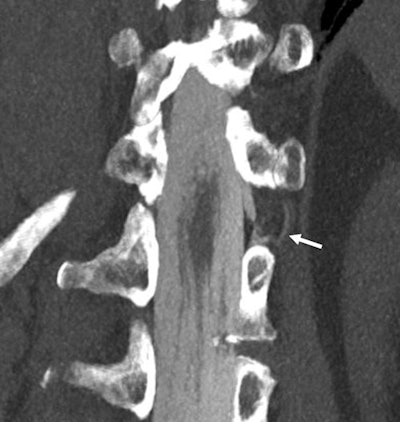

The researchers shared images of a CVF that occurred in a 56-year-old woman and was visualized with both standard CT myelography and with photon-counting CT. CT myelography could not confirm CVF, but the photon-counting image could -- which led to better-tailored treatment.

Coronal 3-mm maximum intensity projection image of a CSF-venous fistula (arrow indicates the iodinated contrast in the fistula). This was not detected on regular clinical CT with a 0.6-mm resolution but was clearly depicted on a newly U.S. Food and Drug Adminstration-approved photon-counting CT scanner with 0.2-mm resolution. Images and caption courtesy of Dr. Fides Schwartz."We had only hoped for this new technology to be able to depict these very small structures better than the current clinical standard and were very excited to actually see how the higher spatial resolution of 0.2 mm in combination with the material decomposition capabilities were improving our diagnostic capabilities," Schwartz told AuntMinnie.com.